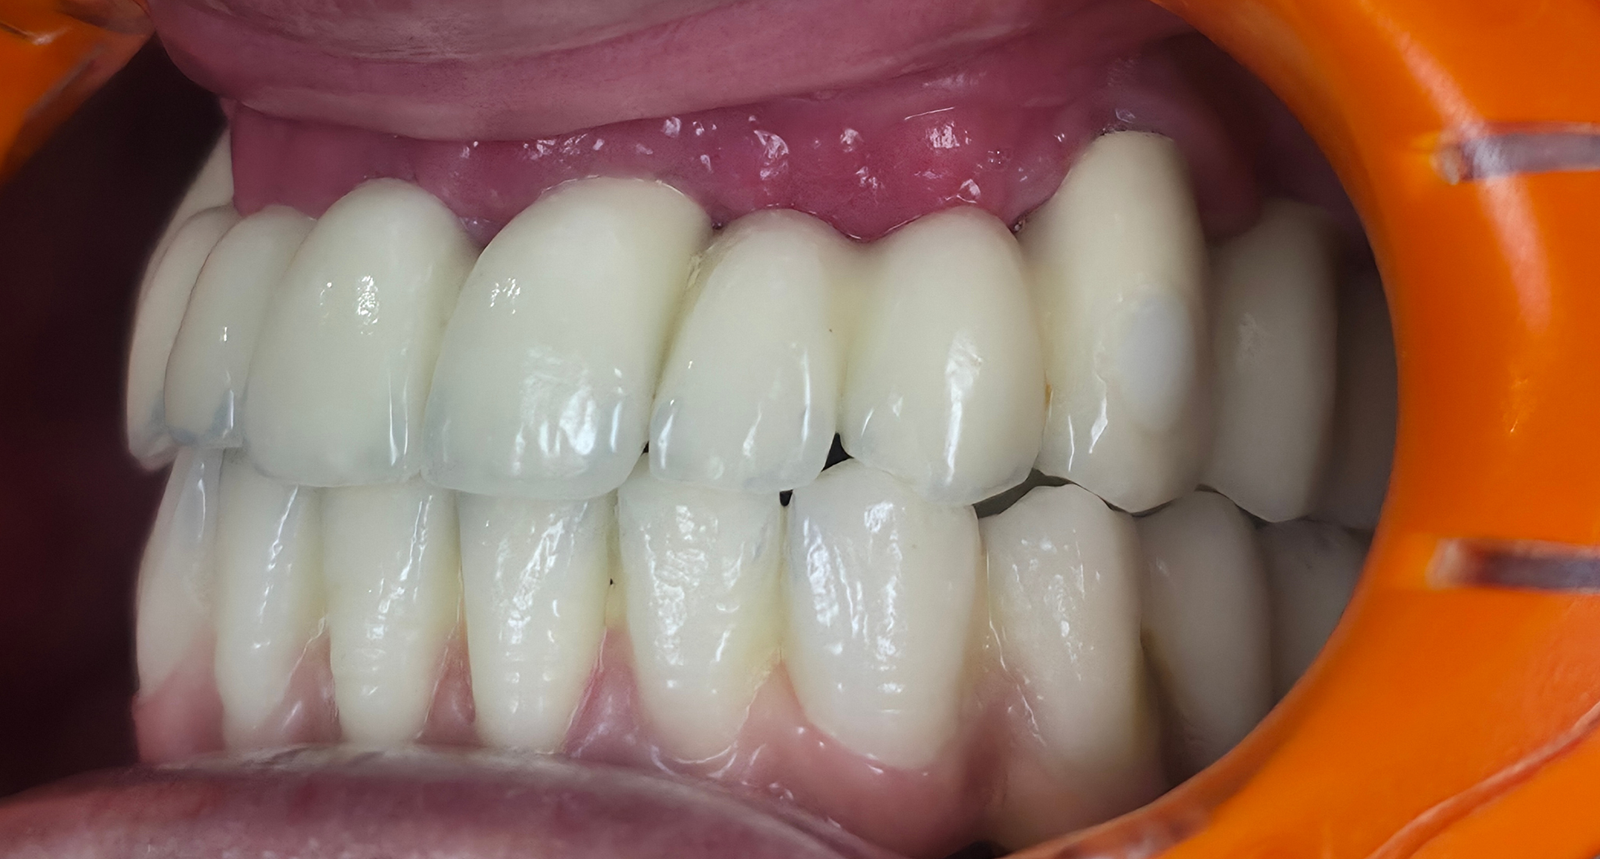

Réhabilitation complète avec mise en charge immédiate (4 implants bas / 6 implants haut)

Le patient se présente avec des dents qui bougent, en haut et en bas.

Nous avons commencé par la mâchoire inférieure avec 4 implants et une mise en charge immédiate.

Trois mois après, le haut a été fait avec le même principe avec 6 implants.

Cette fois-ci, il existait un déficit osseux, résolu par une technique d’expansion sans avoir recours à la greffe d’os.

Les prothèses réalisées sont vissées, ce qui permet de les enlever, les nettoyer une fois par an, ou résoudre n’importe quel problème.